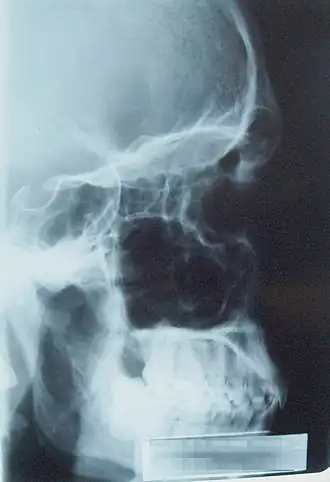

Les sinus paranasaux sont un groupe de quatre paires de cavités remplies d'air où l'orifice d'entrée de l'air et celui de sortie ne font qu'un, autour des cavités nasales et contenues dans les os crâniens.

Il existe quatre types de sinus paranasaux :

- Le sinus maxillaire : Le plus sujet à des pathologies. Asymétriques, on trouve un sinus maxillaire droit et un sinus maxillaire gauche. Ils constituent le type le plus volumineux de sinus. Se formant vers 2 ans, son volume va croître considérablement avec le développement de la face, ce qui permet d’alléger le massif facial. Il a une forme de pyramide couchée dont la base répond à la paroi latérale de la cavité nasale et le sommet au processus zygomatique du maxillaire - La face supérieure du sinus maxillaire répond à la face inférieure de la cavité orbitaire - La paroi postérieure est en rapport avec la fosse infra-temporale - Bord inférieur en rapport essentiel avec la région alvéolaire du maxillaire : les racines dentaires ;

- Le sinus frontal : Descend dans les fosses nasales par le canal naso-frontal qui s’abouche à la partie antérieure de la région du hiatus maxillaire. Certains parlent de sinus frontaux (au pluriel) car il est cloisonné avec 2 ou 3 parois orientées dans un plan sagittal ;

- Les sinus ethmoïdaux : Au nombre de 10 à 20, ils sont présents à la naissance. Il ne s'agit pas d'une cavité unique comme les autres sinus mais plusieurs cloisonnements qui forment un labyrinthe au niveau de la masse latérale de l’ethmoïde. On les décrit en 2 parties : cellules ethmoïdales antérieures et postérieures. La partie antérieure des cellules ethmoïdales s’ouvre au niveau du méat nasal moyen et la partie postérieure au niveau du méat nasal supérieur. Les cellules ethmoïdales constituent la paroi médiale de l’orbite ;

- Le sinus sphénoïdal : A l’intérieur du corps du sphénoïde. Rapports : Au-dessus : loge hypophysaire - selle turcique, Latéralement : sinus caverneux, En dessous : les fosses nasales. Il communique avec les fosses nasales par le récessus sphéno-ethmoïdal.